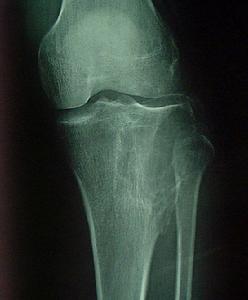

疾病描述:巨細胞瘤很可能起源於骨髓結締組織間充質細胞,以基質細胞核和多核巨細胞為主要結構,是一種潛在惡性或介於良好惡之間溶骨性腫瘤。好發年齡20-40歲,性別差異不大,好發部位為股骨下端和脛骨上端。X線片表現:骨骺處有局限的囊性改變,一般呈溶骨性破壞,也可有“肥皂泡”樣改變,其擴展一般為軟骨所限。不破入關節,少有骨膜反應,腫瘤範圍清楚,初發時病變在骨骺內旁側,發展後可占骨端的全部,骨皮質膨脹變薄,有的可以穿破,進入軟組織。X線片可顯示其一般特點,但仍不足以確診。主要的症狀為疼痛和腫脹,與病情的發展相關,局部包塊壓之有桌球樣感覺,病變的關節活動受限。骨巨細胞瘤多發生於四肢長骨的骨骺端,尤以股骨下端及脛骨上端為多見,約占半數左右,其次為橈骨下端、尺骨下端或肱骨上端等部位。長骨以外則以脊椎為多見。

X線主要表現為骨端變心位溶骨性破壞而無滑膜反應,病灶骨皮質膨脹變薄,呈肥皂泡樣改變。

X線片表現:骨骺處有局限的囊性改變,一般呈溶骨性破壞,也可有“肥皂泡”樣改變,其擴展一般為軟骨所限。不破入關節,少有骨膜反應,腫瘤範圍清楚,初發時病變在骨骺內旁側,發展後可占骨端的全部,骨皮質膨脹變薄,有的可以穿破,進入軟組織。X線片可顯示其一般特點,但仍不足以確診。

GCT臨床病理特徵 好發20歲~40歲青壯年,男女發病差別不大,特發部位為長骨骺端,尤以股骨下端、脛骨上端、橈骨下端多見。鏡下由單核基質細胞和多核巨細胞構成,多核巨細胞數量多,均勻分布,間質出血明顯。GCT具有明顯的局部侵襲性,復發率高,並可發生轉移,用原來的腫瘤病理組織學分級預測預後,並非絕對可靠。